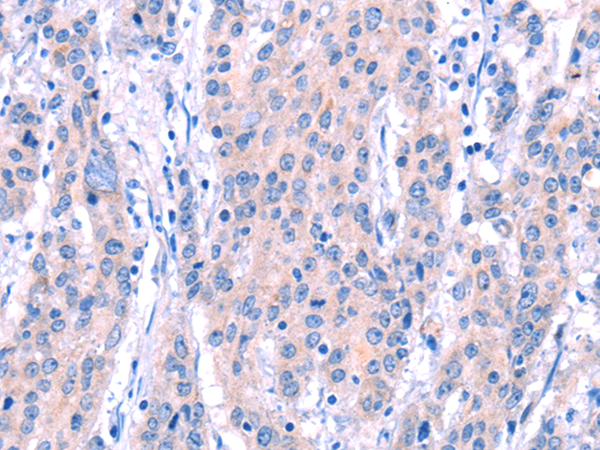

分类: 科研抗体货号: P04845别名: p43; HLD3; EMAP2; SCYE1; EMAPII应用: WB,IHC反应种属: Human, Mouse